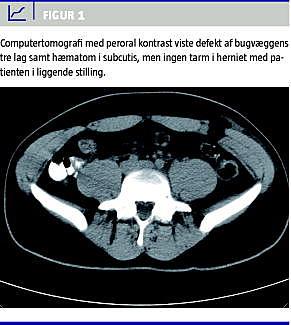

Akut computertomografi (CT) viste en defekt på 3 cm i muskulatur og fascie uden relation til rectusskeden (Figur 1 ). Patienten blev udskrevet med elastikbind og analgetika til laparoskopisk ventralhernio-tomi efter fire uger.